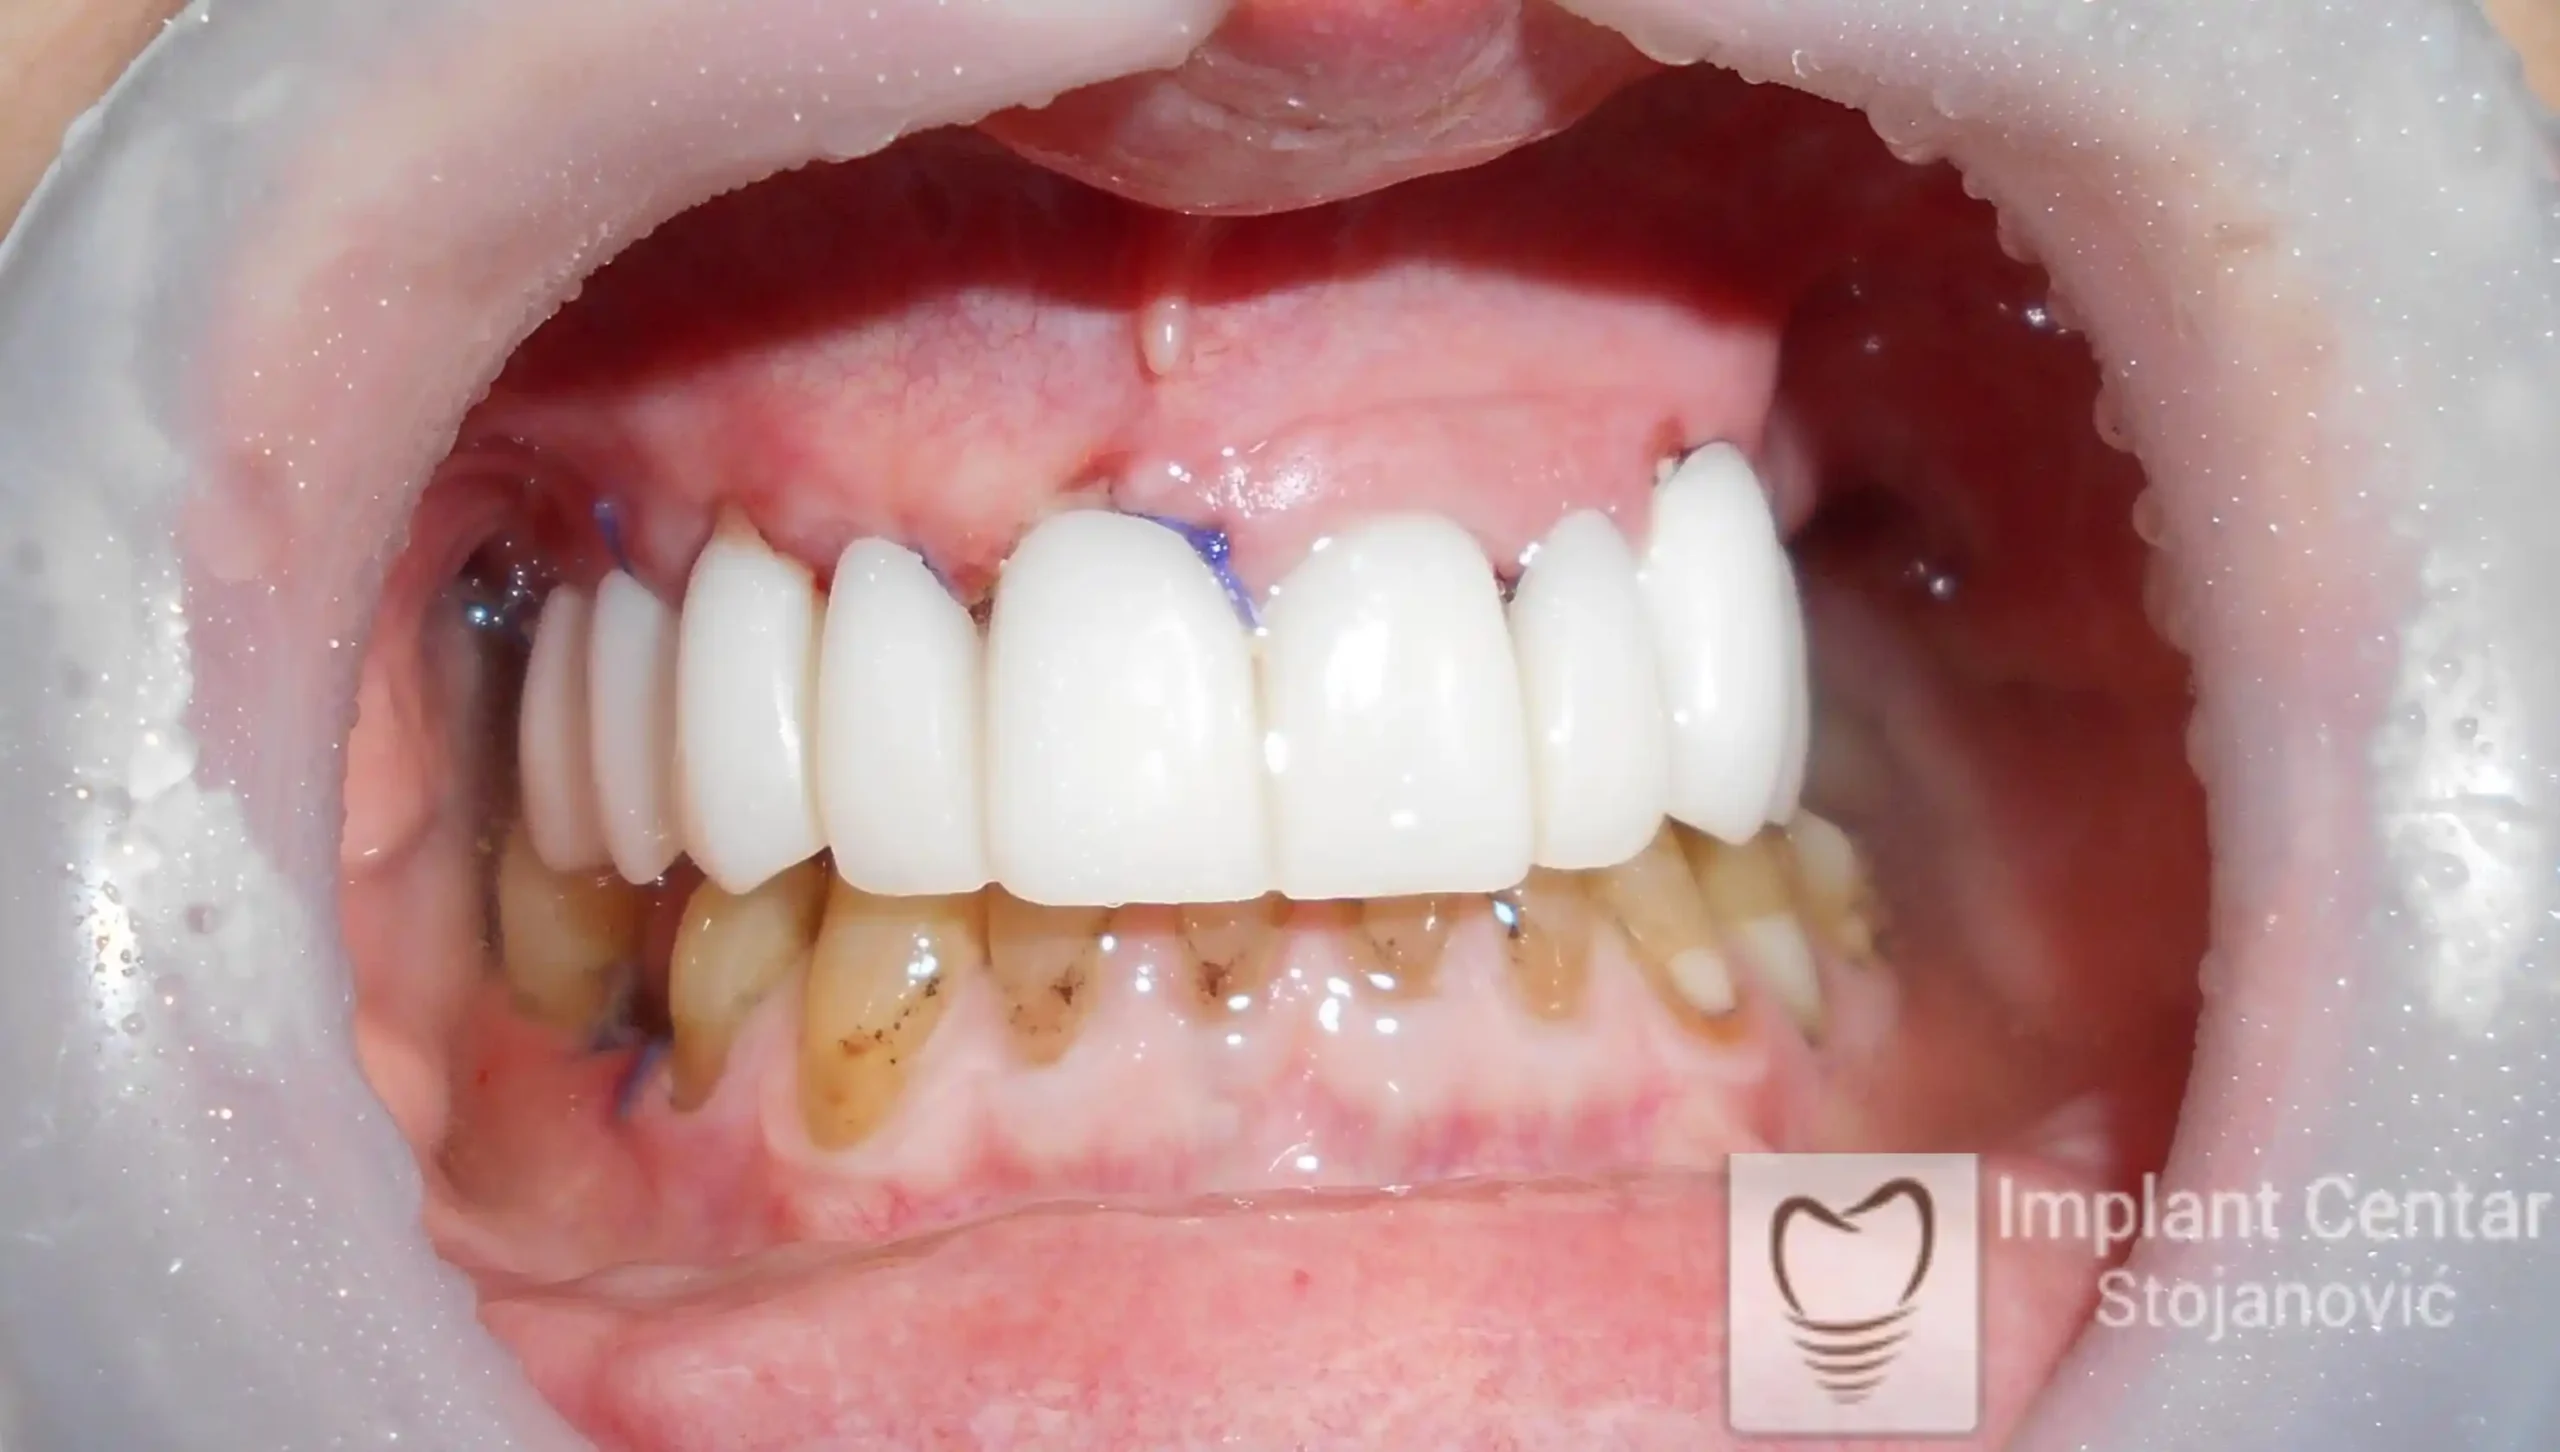

Pacijentkinja je došla sa dotrajalim mostovima i preostalim zubima loše biološke vrednosti, dok su bezubi prostori bili prisutni u gornjoj vilici sa desne strane i  u donjoj vilici sa leve strane. Nakon detaljnog kliničkog pregleda i analize snimaka, izvršeno je vađenje svih zuba i ugradnja optimalnog broja dentalnih implantata.

Već tri dana nakon operacije pacijentkinja je zbrinuta privremenim krunicama, kojima je bila oduševljena jer su odmah omogućile funkciju i estetiku. Nakon perioda oseointegracije izrađene su definitivne cirkonijum-keramičke krunice, čime je postignuta maksimalna estetika, funkcija i vraćeno samopouzdanje. Pacijentkinja je presrećna postignutim rezultatom.